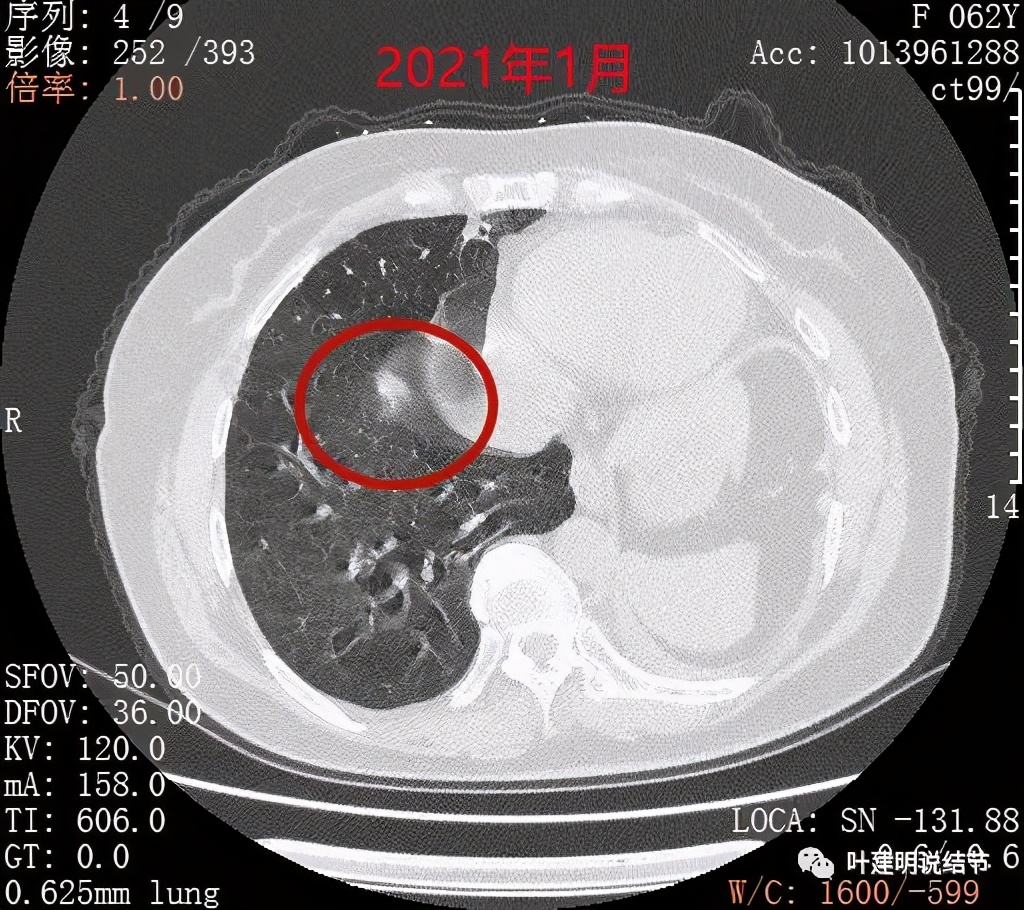

到了一年后,这结节没有吸收好转,反而边上较前清楚了一点起来,仍像磨玻璃过渡到实性的阶段(偏实性,但又不是很密实)

到了今年1月份时,结节还在,瘤肺边界似较前清楚了点